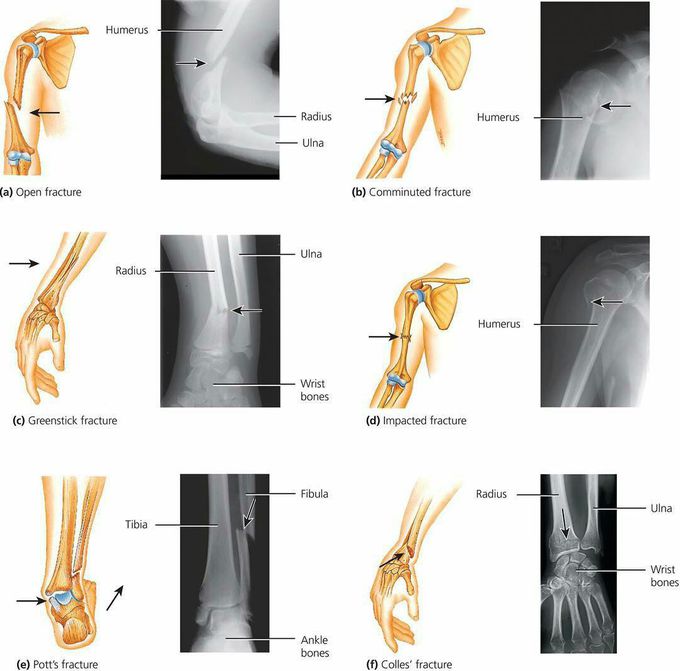

Types of fractures

Fracture

Bones